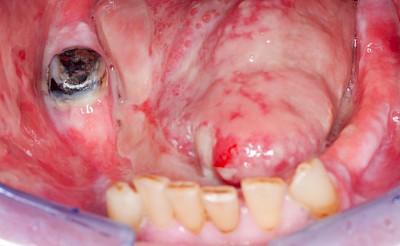

Wundheilungsstörungen

Nach operativen Eingriffen im Bereich der Mundhöhle (Zahn ziehen "Extraktion", Schleimhautprobenentnahmen "Biopsien" oder Tumoroperationen) kann es zu Wundheilungsstörungen mit Schwellungen, Rötungen und Nach-Blutungen, gestörter Sprache oder Kaufunktion kommen. Einzele Gesichtsbereiche können sich warm anfühlen und in seltenen Fällen kann es zu Fieber und reduziertem Allgemeinzustand kommen.

Wundheilungsstörungen24 Bilder